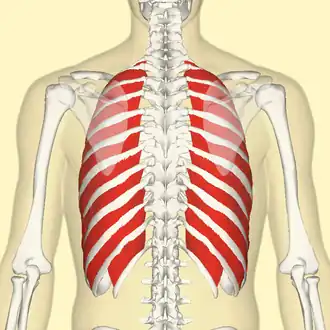

Position of the external intercostal muscles (shown in red) seen from the back. | |

The external intercostal muscles or external intercostals (intercostales externi) are eleven in number on both sides.

The muscles extend from the tubercles of the ribs behind, to the cartilages of the ribs in front, where they end in thin membranes, the external intercostal membranes, which are continued forward to the sternum. These muscles work in unison when inhalation occurs. The internal intercostal muscles relax while the external muscles contract causing the expansion of the chest cavity and an influx of air into the lungs.

They are thicker than the internal intercostals, and their fibers are directed obliquely downward and laterally on the back of the thorax, and downward, forward, and medially on the front.

Position of the external intercostal muscles (shown in red). Animation.

Position of the external intercostal muscles (shown in red). Animation. -